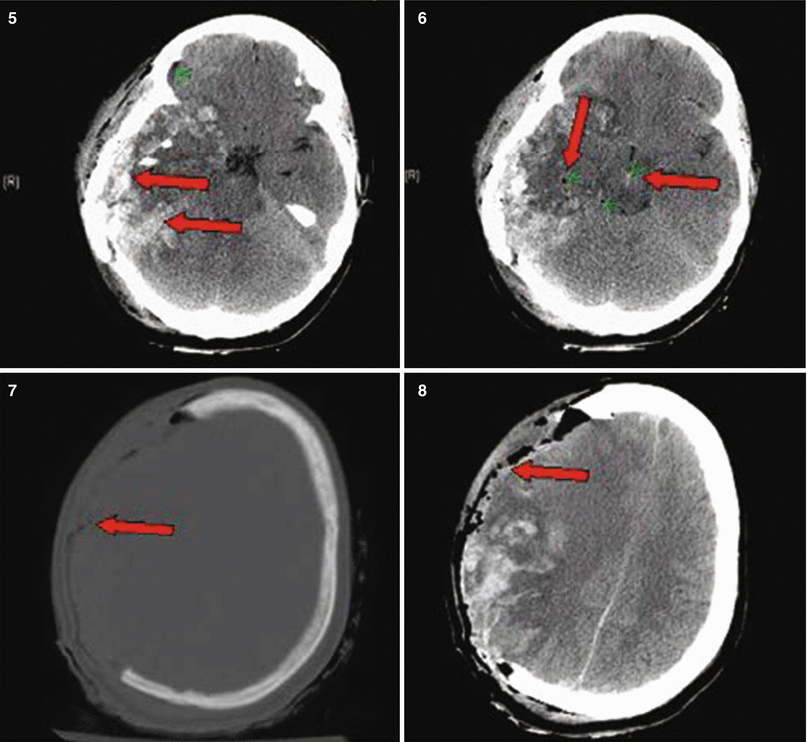

Fig. 27.3

Patient No. 3: a 30-year-old female, who sustained a solitary GSW to the back of her head from close range. Entry wound on the occiput and no exit wound. Arrow in plates 1 and 2 points at the retained bullet case. Arrow in plate 3 shows the bullet case as seen in the corresponding head CT on axial CT bone window. Arrows in plate 4 point at a dilated right lateral ventricle and at left perimesencephalic hemorrhage. Arrows in plate 5 show the enlarging hematoma in the CP angle and a hematoma in the left sided posterior fossa. Arrow in plate 6 shows the bilateralsuboccipital craniectomy site that was created to gain access for evacuation. Arrow in plate 7 points at the evatuation side of the previously seen hematoma in 5. Arrow in plate 8 points at the R frontal EVD catheter inserted to treat the occlusive hydrocephalus